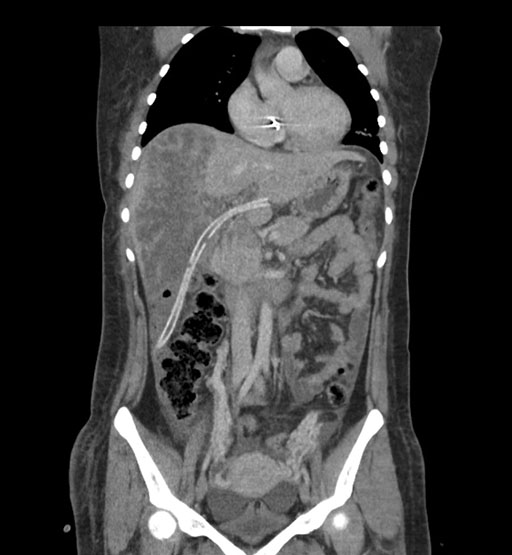

Imaging Analysis

Look through the patient's CT scan to identify any areas of concern for the necessary procedure.

Coronal Arterial

Coronal Venous

Based on initial findings, which issue(s) would you be most concerned about?